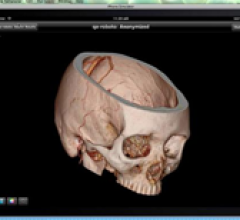

August 19, 2011 – Cell Therapeutics Inc. announced that enrollment has opened for a randomized phase II clinical study comparing the combination of Opaxio (paclitaxel poliglumex, PPX) and radiation to the combination of temozolomide (TMZ) and radiation for patients with newly diagnosed glioblastoma, a high-grade malignant brain tumor.